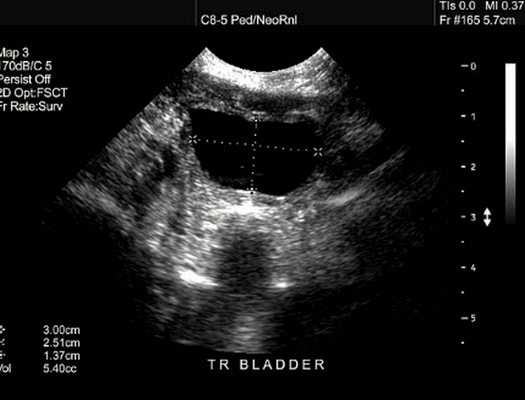

Ультразвуковая диагностика опухолей мочевого пузыря

Частота ультразвуковых признаков при опухолях мочевого пузыря различна. Важнейшим симптомом опухолевого поражения мочевого пузыря является симптом тканевого пристеночного образования мочевого пузыря у ряда пациентов признак локального утолщения и неравномерности стенки мочевого пузыря.

На УЗИ обычно выявляется одно образование с неравномерными, расплывчатыми контурами, главным образом изоэхогенное стенке мочевого пузыря и умеренно неоднородной эхоструктуры. Увеличение стенки в области опухоли мочевого пузыря и модификация ее эхоструктуры позволяет предположить глубокую инвазию опухоли. Если необходимо установить связь опухоли и предстательной железы, то применяется трансректальное УЗИ.

Основным симптомом опухолевого процесса в мочевом пузыре на ультразвуковом сканировании будет выявление дефекта наполнения в его просвете в виде симптома экзофитного интравезикального солидного очага. Особенности метода ультразвукового исследования, позволяющие получать изображения различных сечений исследуемых объектов‚ дает возможность сделать полипозиционное и полипроекционное исследование всех без исключения отделов стенки мочевого пузыря. Это позволяет выявлять случаи мультифокального поражения. По нашему опыту работы в Красноярске, самая маленькая опухоль, выявленная на трансабдоминальном УЗИ, была равна в ширину 5 мм, а в высоту 6 мм.